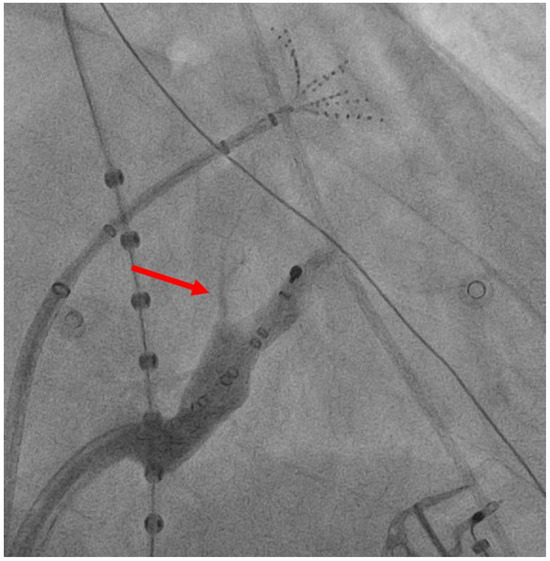

3.2. VoM Ethanol Infusion

5. Technique for VoM Ethanol Infusion

- Valderrábano, M.; Chen, H.R.; Sidhu, J.; Rao, L.; Ling, Y.; Khoury, D.S. Retrograde ethanol infusion in the vein of Marshall: Regional left atrial ablation, vagal denervation and feasibility in humans. Circ. Arrhythmia Electrophysiol. 2009, 2, 50–56. [Google Scholar] [CrossRef]

- Valderrábano, M.; Liu, X.; Sasaridis, C.; Sidhu, J.; Little, S.; Khoury, D.S. Ethanol Infusion in the Vein of Marshall: Adjunctive Effects during Ablation of Atrial Fibrillation. Heart Rhythm Off. J. Heart Rhythm Soc. 2009, 6, 1552–1558. [Google Scholar] [CrossRef]

- Kamakura, T.; Derval, N.; Duchateau, J.; Denis, A.; Nakashima, T.; Takagi, T.; Ramirez, F.D.; André, C.; Krisai, P.; Nakatani, Y.; et al. Vein of Marshall Ethanol Infusion: Feasibility, Pitfalls, and Complications in Over 700 Patients. Circ. Arrhythm. Electrophysiol. 2021, 14, e010001. [Google Scholar] [CrossRef] [PubMed]